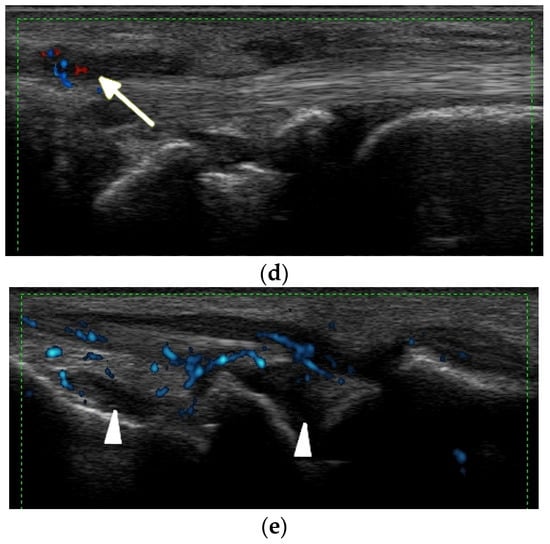

Typical for SLE are spontaneous tendon ruptures (Figure 6, Figure 7 and Figure 8), most commonly of the patellar and Achilles tendons. In SLE, inflammatory changes as well as tears may be observed not only on the background of tenosynovitis, but also involving the tendon in the absence of tenosynovitis, even along the intramuscular segment [] (Figure 8).

Figure 6.

A complete spontaneous tear of the right posterior tibialis tendon (PTT) 2 cm above the medial malleolus in a 46-year-old female with systemic lupus erythematosus. (a,b) short-axis gray-scale ultrasound (US) images of the medial aspect of the bilateral ankles show the normal echogenic fibrillar appearance of the healthy left PTT (a, arrow) compared to an enlarged, torn right hypoechoic PTT in the same region between calipers in (b). (c) Short-axis power Doppler US image of the affected right side shows hyperemia in the PTT tendon stump, with additional hyperemia in the tendon sheath consistent with tendinopathy and tenosynovitis. Two tiny red dots at the periphery of green Doppler box represent normal vessels.

Figure 7.

A complete tear of the proximal part of the bare tendon of the distal biceps brachii bilaterally in the same patient as in Figure 6. Short-axis (a,b) and long-axis (c,d) gray-scale ultrasound images of the bilateral elbow/distal arms show rupturing of the bilateral distal biceps tendons at the level of the myotendinous junction with hypoechoic proximal stums consistent with tendinopathy (arrows). In (c,d), note the retracted bilateral biceps muscles.